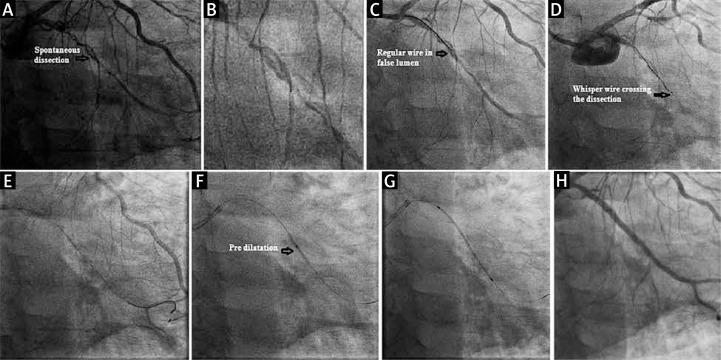

Three cases of successful angioplasty of high-grade coronary dissections using hydrophilic wires were reported. Our first case had edge dissection after a stent deployed in the left anterior descending artery, after which we found it impossible to track the second stent over the regular wires, and which was successful when we tried with a stiffer hydrophilic wire. The second had spontaneous coronary artery dissections (SCAD), and the third case was a complicated plaque with multiple stenotic and ectatic segments along with dissection and successful angioplasty carried out using the same wires and without additional hardware. These wires also provided adequate support in tracking the required balloons and stents.